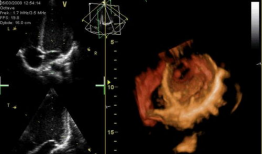

心脏跳动的视频,揭秘心脏跳动的奥秘

你知道吗?最近在网上流传着一个特别神奇的视频,它记录了心脏跳动的瞬间。这可不是普通的视频,它让我们仿佛能感受到心跳的力量,那种感...